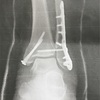

足関節脱臼骨折の記録

抜釘手術 骨折1年16日

外側は前の傷のとおり、内側はネジ回すだけのちっさなキズですんだそう。ニコニコしてた。これでキズ治って動けてたら終了できるそうです⤴︎